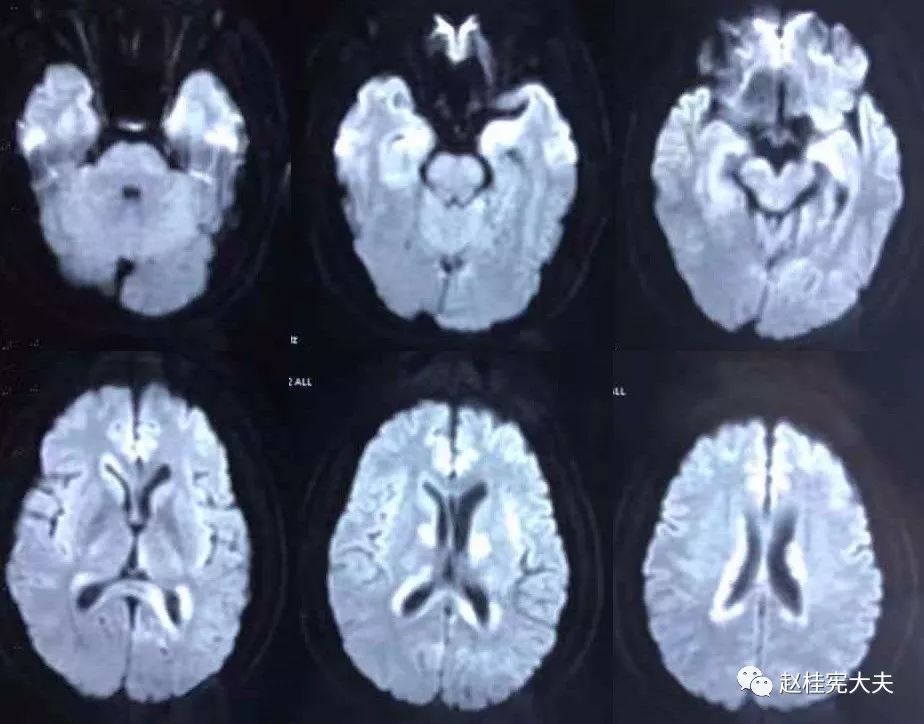

2018.7.6头颅MRI:胼胝体、穹隆及双侧脑室旁、基底节区、右侧延髓、桥臂异常信号,脱髓鞘病变考虑。头颅MRS:左枕叶病变区MRS显示:NAA下降,Cho升高,Cho/NAA=3.86,并见倒置乳酸峰。

我看到患者时的思考:当了解了患者前期诊疗经过后,在看到患者磁共振片子时,我的第一反应就是淋巴瘤。尽管患者激素治疗后症状有好转,病灶在磁共振上看起来也是有好转,但淋巴瘤也会出现这样的表现。

我对满脑室边的病灶的体会是:遇到这样的病例,首先要考虑感染、肿瘤(如室管膜瘤、生殖细胞瘤、淋巴瘤或转移瘤脑室播散等等),炎症要放到后面去考虑,脱髓鞘的诊断要打个大大大大的?。炎症中,血管炎不像,自免脑也不是很支持,尽管边缘系统似乎也有受累,但患者边缘叶脑炎的精神、行为异常、癫痫等症状很少,而且磁共振上看去除了边缘系统,整个脑室系统都有受累,这个和常见自免脑不符。视神经脊髓炎谱系病?尽管病灶在水通道蛋白富集区,但这样的视神经脊髓炎(视神经和脊髓均未受累,近脑室边的异常信号)至少罕见,即使诊断,也应该是排除其它的疾病后才可能考虑。

患者住院期间还请眼科会诊,除双眼玻璃体轻度浑浊,视力、视野、OCT均未见明显异常,未建议行玻切明确诊断。患者入院后嗜睡症状有加中,但一直未诉头痛,仅是头昏,静滴甘露醇症状减轻不明显。复查头颅磁共振平扫+增强:病灶范围较前明显扩大。轻度强化。